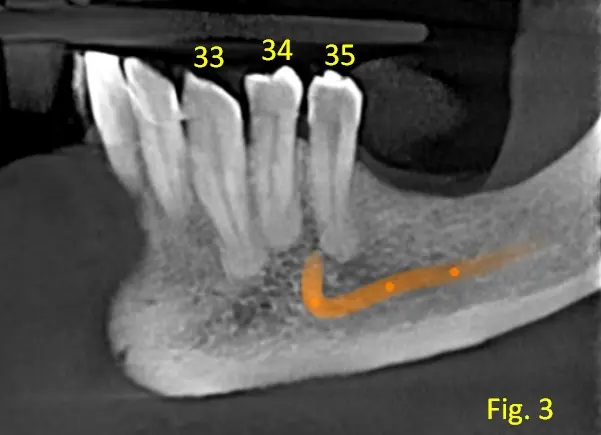

La presentación de casos radiográficos, permite la visualización de patologías que son muy difíciles de ver en la clínica, ya que muchos de ellos son hallazgos radiográficos. Además permite ver y refrescar clasificaciones y conceptos muchas veces estudiados. La presentación de los mismos no incluyen datos personales, mas que edad y sexo, que suelen ser importantes para ver la correlación entre la patología, su aparición o forma de presentación.

Caso N°